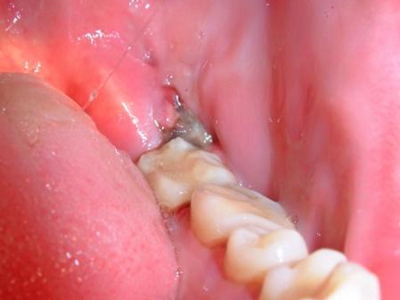

阻生牙是指由于邻牙、骨或软组织的阻碍而只能部分萌出或完全不能萌出,且以后也不能萌出的牙。引起牙阻生的成因,主要是由于颌骨缺乏足够的空间容纳全部恒牙。常见的阻生牙为下颌第三磨牙、上颌第三磨牙及上颌尖牙。

阻生牙可反复引起冠周炎,或引起邻牙牙根吸收和破坏,位置不正,不能完全萌出,好发部位是上、下颌第三磨牙。

对于阻生牙的处置需要首先明确阻生牙齿发育情况是否正常,对于由于早期外伤或其他原因造成发育异常,如牙根弯曲、短根等情况的阻生牙,还应根据患者的综合情况,决定牙齿是否保留。